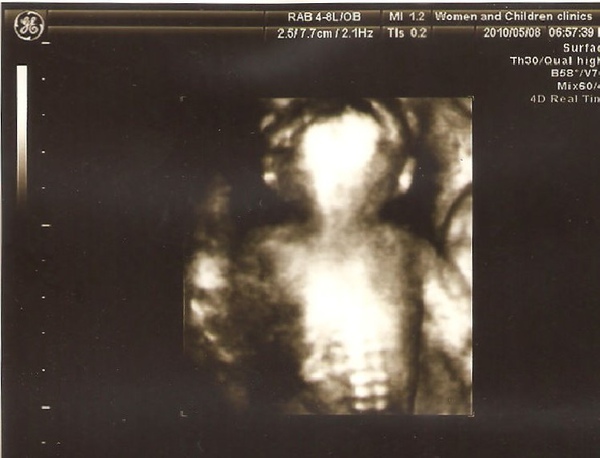

這張是啥鬼東西!要拍的那個moment給我來個大翻身嗎?